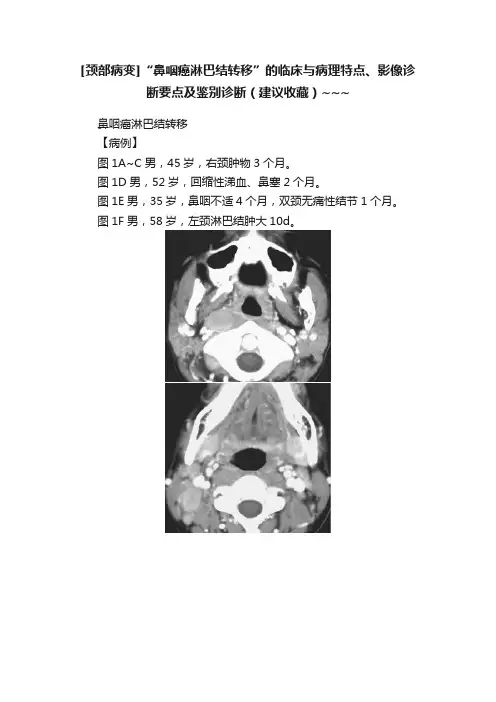

[颈部病变]“鼻咽癌淋巴结转移”的临床与病理特点、影像诊断要点及鉴别诊断(建议收藏)~~~鼻咽癌淋巴结转移【病例】图1A~C男,45岁,右颈肿物3个月。

图1D男,52岁,回缩性涕血、鼻塞2个月。

图1E男,35岁,鼻咽不适4个月,双颈无痛性结节1个月。

图1F男,58岁,左颈淋巴结肿大10d。

图1【影像所见】图1A~C双侧咽后组、颈上、中深组、颈后三角区淋巴结肿大,边缘规则,密度均匀,中等强化。

图1D左颈上深组淋巴结肿大,边缘规则,边缘呈环状强化,内部呈均匀低密度区。

图1E双颈上深组及左侧腮腺内淋巴结肿大,边缘规则,密度均匀,中等度强化。

图1F双颈中深组及左侧颌下淋巴结肿大,边缘规则,密度均匀,中等度强化。

【病理诊断】均为鼻咽癌淋巴结转移。